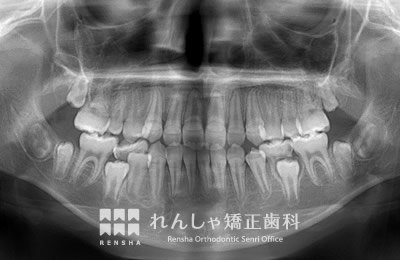

埋伏(まいふく)

永久歯が埋まったまま自然に萌出しないことがあります。周辺の歯に引っかかっていたり、歯胚(歯の卵)の位置や方向が悪い場合、分厚い歯ぐきに覆われている場合など様々です。埋伏している永久歯が隣接する永久歯の歯根を吸収してしまうこともあるので、引っ張り出す処置(牽引処置)が必要になることがほとんどです。場合によっては埋伏歯を抜歯してしまうこともあります。

右上5番目が埋まったままになっているため、スペースを作り引っ張り出しています。

治療前

| 主訴 | 前歯のがたつき |

|---|---|

| 診断名 | Angle Class II 上顎右側第二小臼歯の埋伏を伴う上顎前突 |

| 初診時年齢 | 10歳10か月 |

| 装置名 | マルチブラケット装置 |

| 抜歯非抜歯 | 非抜歯 |

| 治療期間 | 2年1か月 |

| 費用の目安 | 約41万円+消費税(検査料金、都度の処置費用等も合わせた総額) |

| リスク副作用 | 歯の移動に伴う軽微な歯根吸収、歯槽骨吸収、歯肉退縮(いずれも本症例ではほぼ無し)、矯正器具装着中のカリエスリスク増大(本症例ではカリエス発生無し) |